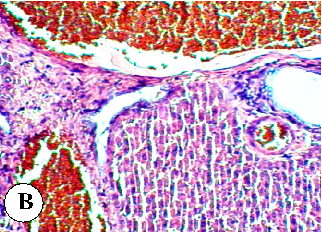

Figure 5

Figure 5 Micrograph

Liver histopathology in diazinon-treated rats showing hepatocellular damage, inflammatory infiltration, and structural changes indicative of pesticide-induced hepatotoxicity.

Protective effect of some plant oils on diazinon induced hepatorenal toxicity in …